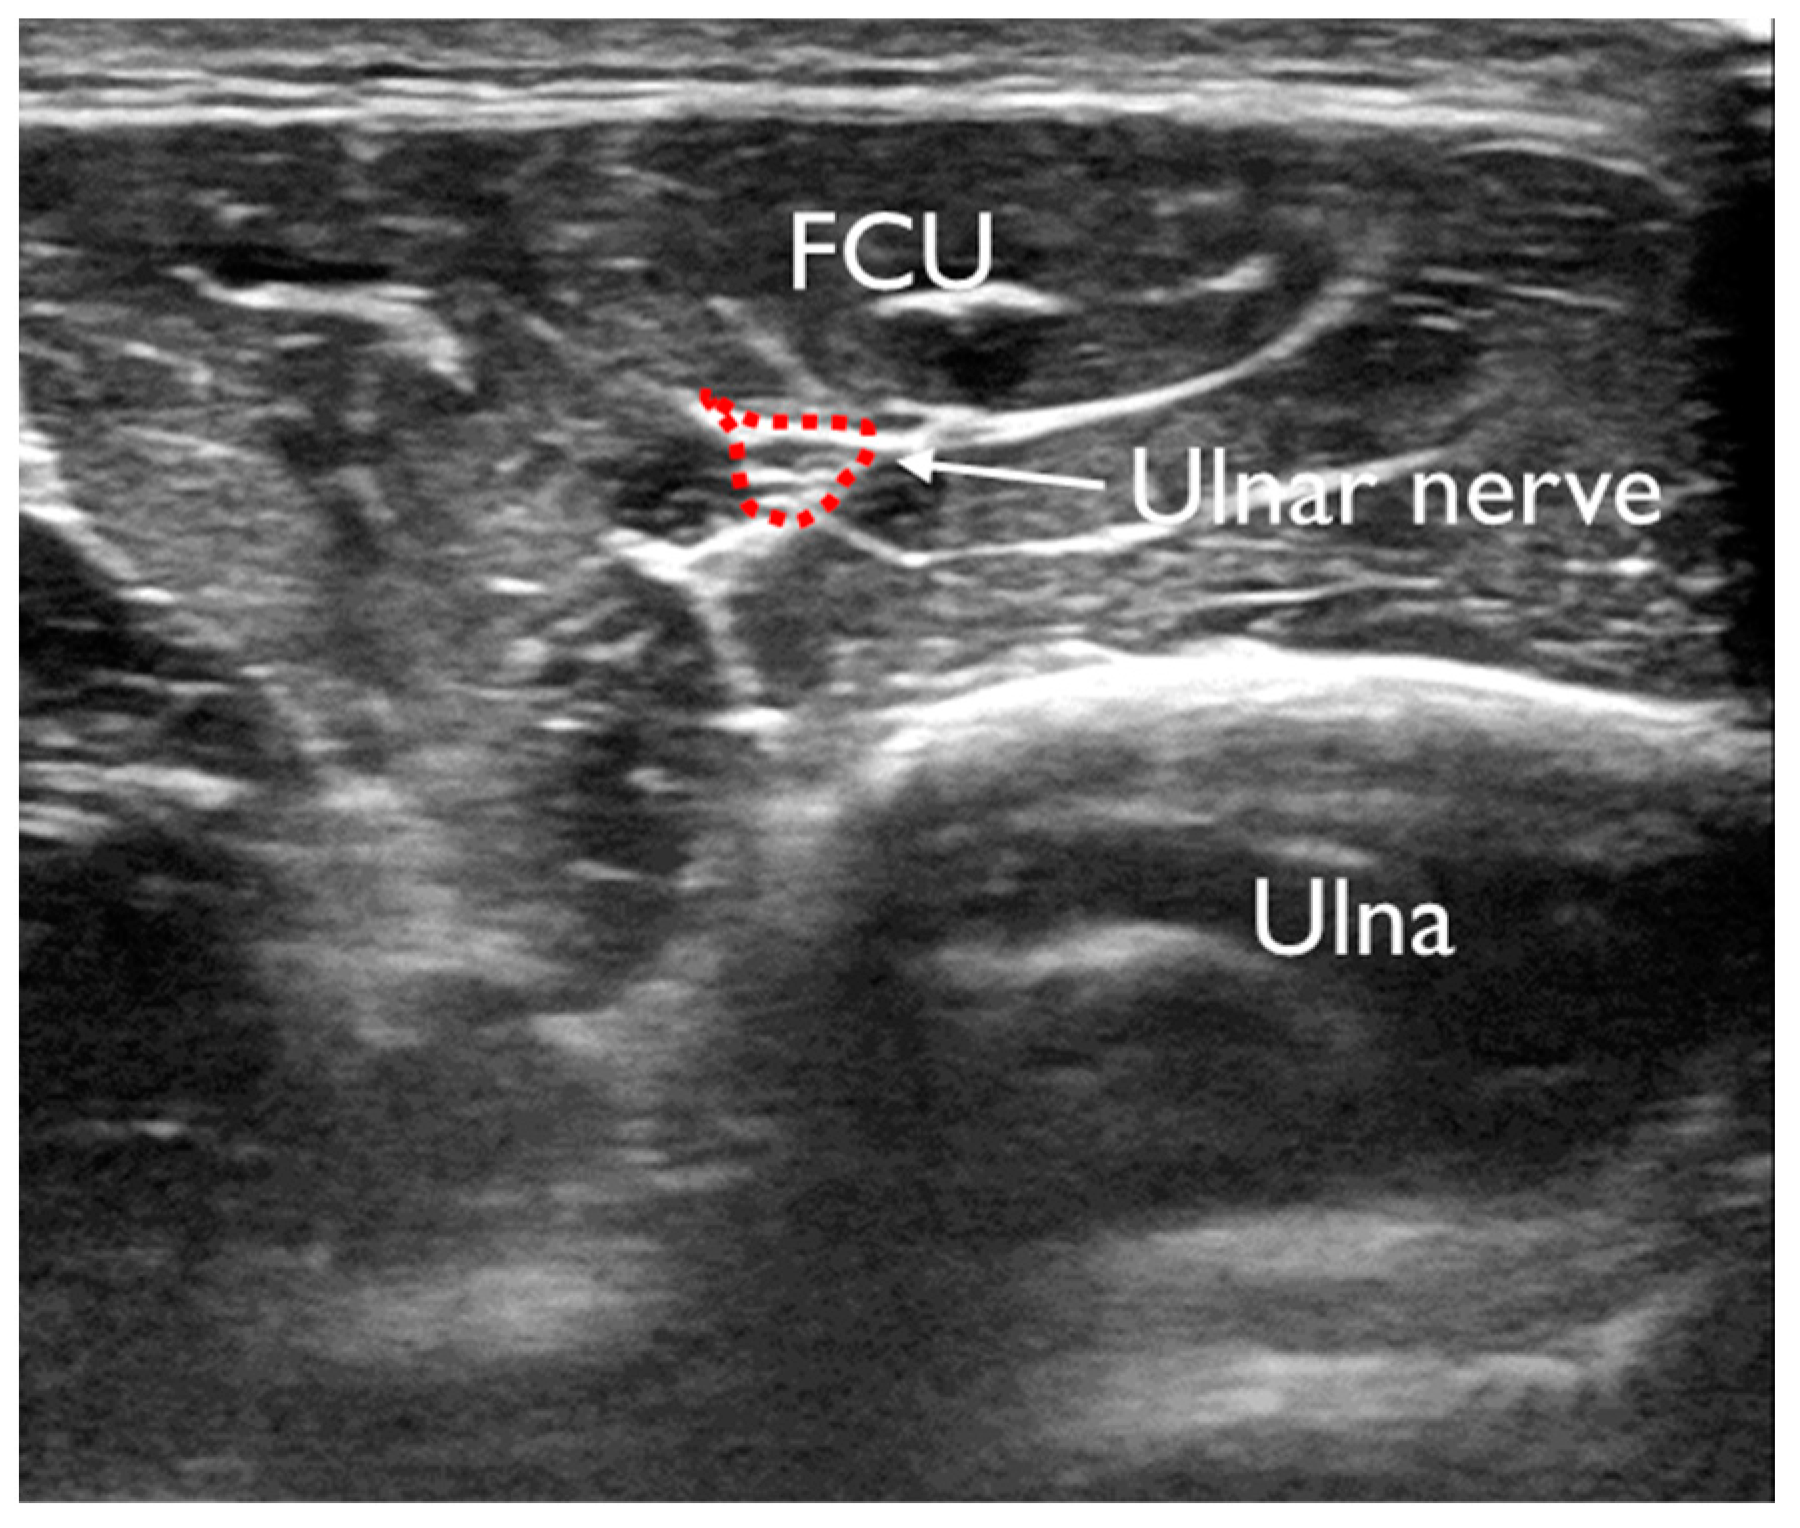

| UN | healthy | 105.0 ± 27.7 | 90.3–119.8 | p = 0.00002 | vs. MER p = 1.75, vs. BR p = 1.11 | vs. MER p = 0.001 **, vs. BR p = 0.01 ** |

| MER | 176.4 ± 53.5 | 143.8–206.1 | vs. BR p = 1.07 | vs. BR p = 0.04 * | ||

| BR | 132.9 ± 21.1 | 120.1–145.6 |

| Rest | Contraction | |||||||

|---|---|---|---|---|---|---|---|---|

| FDP | FCU | FDS | PT | FDP | FCU | FDS | PT | |

| UN | −0.20 | −0.34 * | 0.26 | −0.06 | −0.20 | −0.17 | 0.26 | −0.10 |